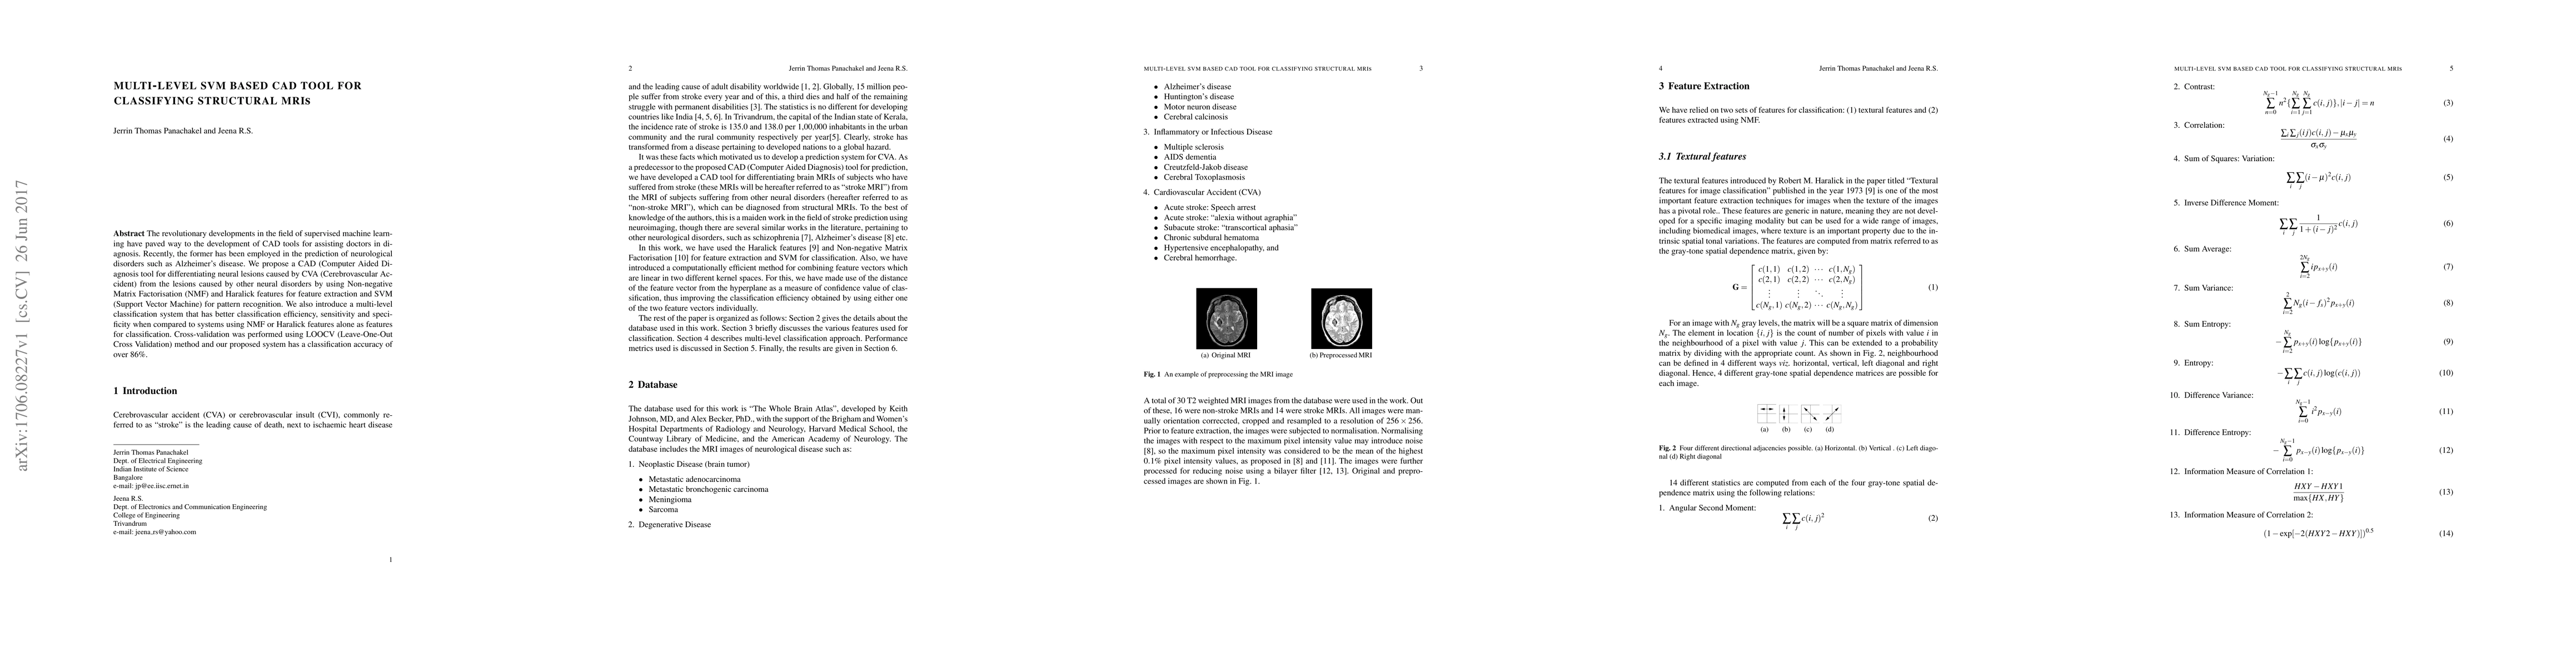

The revolutionary developments in the field of supervised machine learning have paved way to the development of CAD tools for assisting doctors in diagnosis. Recently, the former has been employed in the prediction of neurological disorders such as Alzheimer's disease. We propose a CAD (Computer Aided Diagnosis tool for differentiating neural lesions caused by CVA (Cerebrovascular Accident) from the lesions caused by other neural disorders by using Non-negative Matrix Factorisation (NMF) and Haralick features for feature extraction and SVM (Support Vector Machine) for pattern recognition. We also introduce a multi-level classification system that has better classification efficiency, sensitivity and specificity when compared to systems using NMF or Haralick features alone as features for classification. Cross-validation was performed using LOOCV (Leave-One-Out Cross Validation) method and our proposed system has a classification accuracy of over 86%.